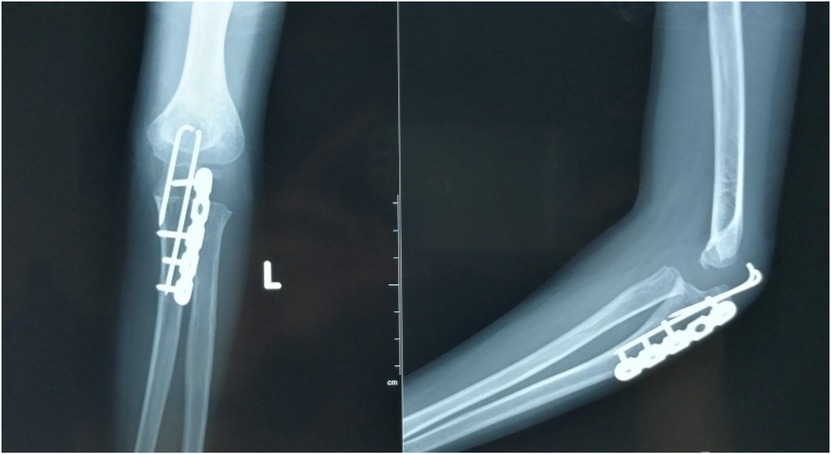

Objective: To investigate and analyze the application value of elbow arthrography in the treatment of chronic radial head dislocation in children. Methods: From January 2014 to January 2017, 15 children with chronic anterior radial head dislocation were treated (11 boys, 4 girls; average age 9 years, range 3-11 years). Intraoperative elbow arthrography was performed to assess the position of the radial head relative to the joint capsule. The nature of the dislocation was confirmed by opening the joint capsule to directly observe the relationship between the radial head and capitellum, as well as the morphology of the radial head. Reduction of the radial head was achieved via proximal ulnar osteotomy, and fixation was performed using a plate and screws with or without Kirschner wires (K-wires). Results: Elbow arthrography showed the radial head was located within the joint capsule in 12 cases and outside the capsule in 3 cases. Among the cases: All 8 congenital dislocations had the radial head within the joint capsule. Of the 7 traumatic dislocations, 4 had the radial head within the capsule and 3 outside. Direct inspection after capsulotomy confirmed the arthrography findings and revealed characteristic morphological differences. In congenital dislocations, there was no scar tissue between the radial head and capitellum, and the radial head fovea was shallow and flat. In traumatic dislocations, obvious scar tissue was present between the radial head and capitellum, and the radial head fovea was distinct. Follow-up ranged from 9 months to 4 years (average 2 years 5 months). Postoperative radiographs showed no cases of radial head re-dislocation or subluxation. Postoperative elbow range of motion improved in all patients, with no reports of pain or functional instability. Conclusion: Elbow arthrography serves as a valuable adjunct for differentiating between congenital and traumatic radial head dislocations, thereby informing both surgical strategy and the decision for supplemental fixation. When stable bony alignment is achieved, proximal ulnar osteotomy without annular ligament reconstruction represents an effective management strategy for chronic radial head dislocation in children.